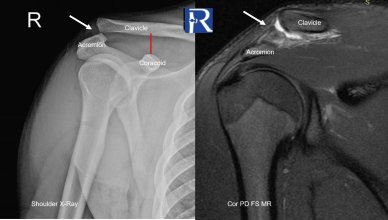

Clinical Presentation A 20-year-old male presented with pain and swelling over the superior aspect of the right shoulder following a motorcycle acc ...

Mehmet Fatih Tumer, MD, and Ozgur Tosun, MD Department of Radiology, Izmir Katip Celebi University, Ataturk Training and Research Hospital, Izmir/T ...

Case Summary A 70-year-old male presented with shoulder pain after a fall. Initial computed tomography (CT) demonstrated a linear, nondisplaced fra ...